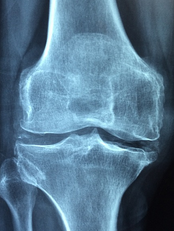

1. **관절 통증 완화**: MSM은 관절의 주요 구성 성분으로, 관절의 유연성을 증진시키고 연골 기능을 유지합니다. 또한, 강력한 항염증 효과를 통해 관절 통증과 부기를 완화하는 데 도움을 줍니다. 한 연구에서는 관절염 환자들이 12주간 MSM을 섭취한 결과 관절 통증, 뻣뻣함, 부기, 관절 기능의 불편함이 줄어들면서 삶의 질이 개선되는 것으로 나타났습니다.